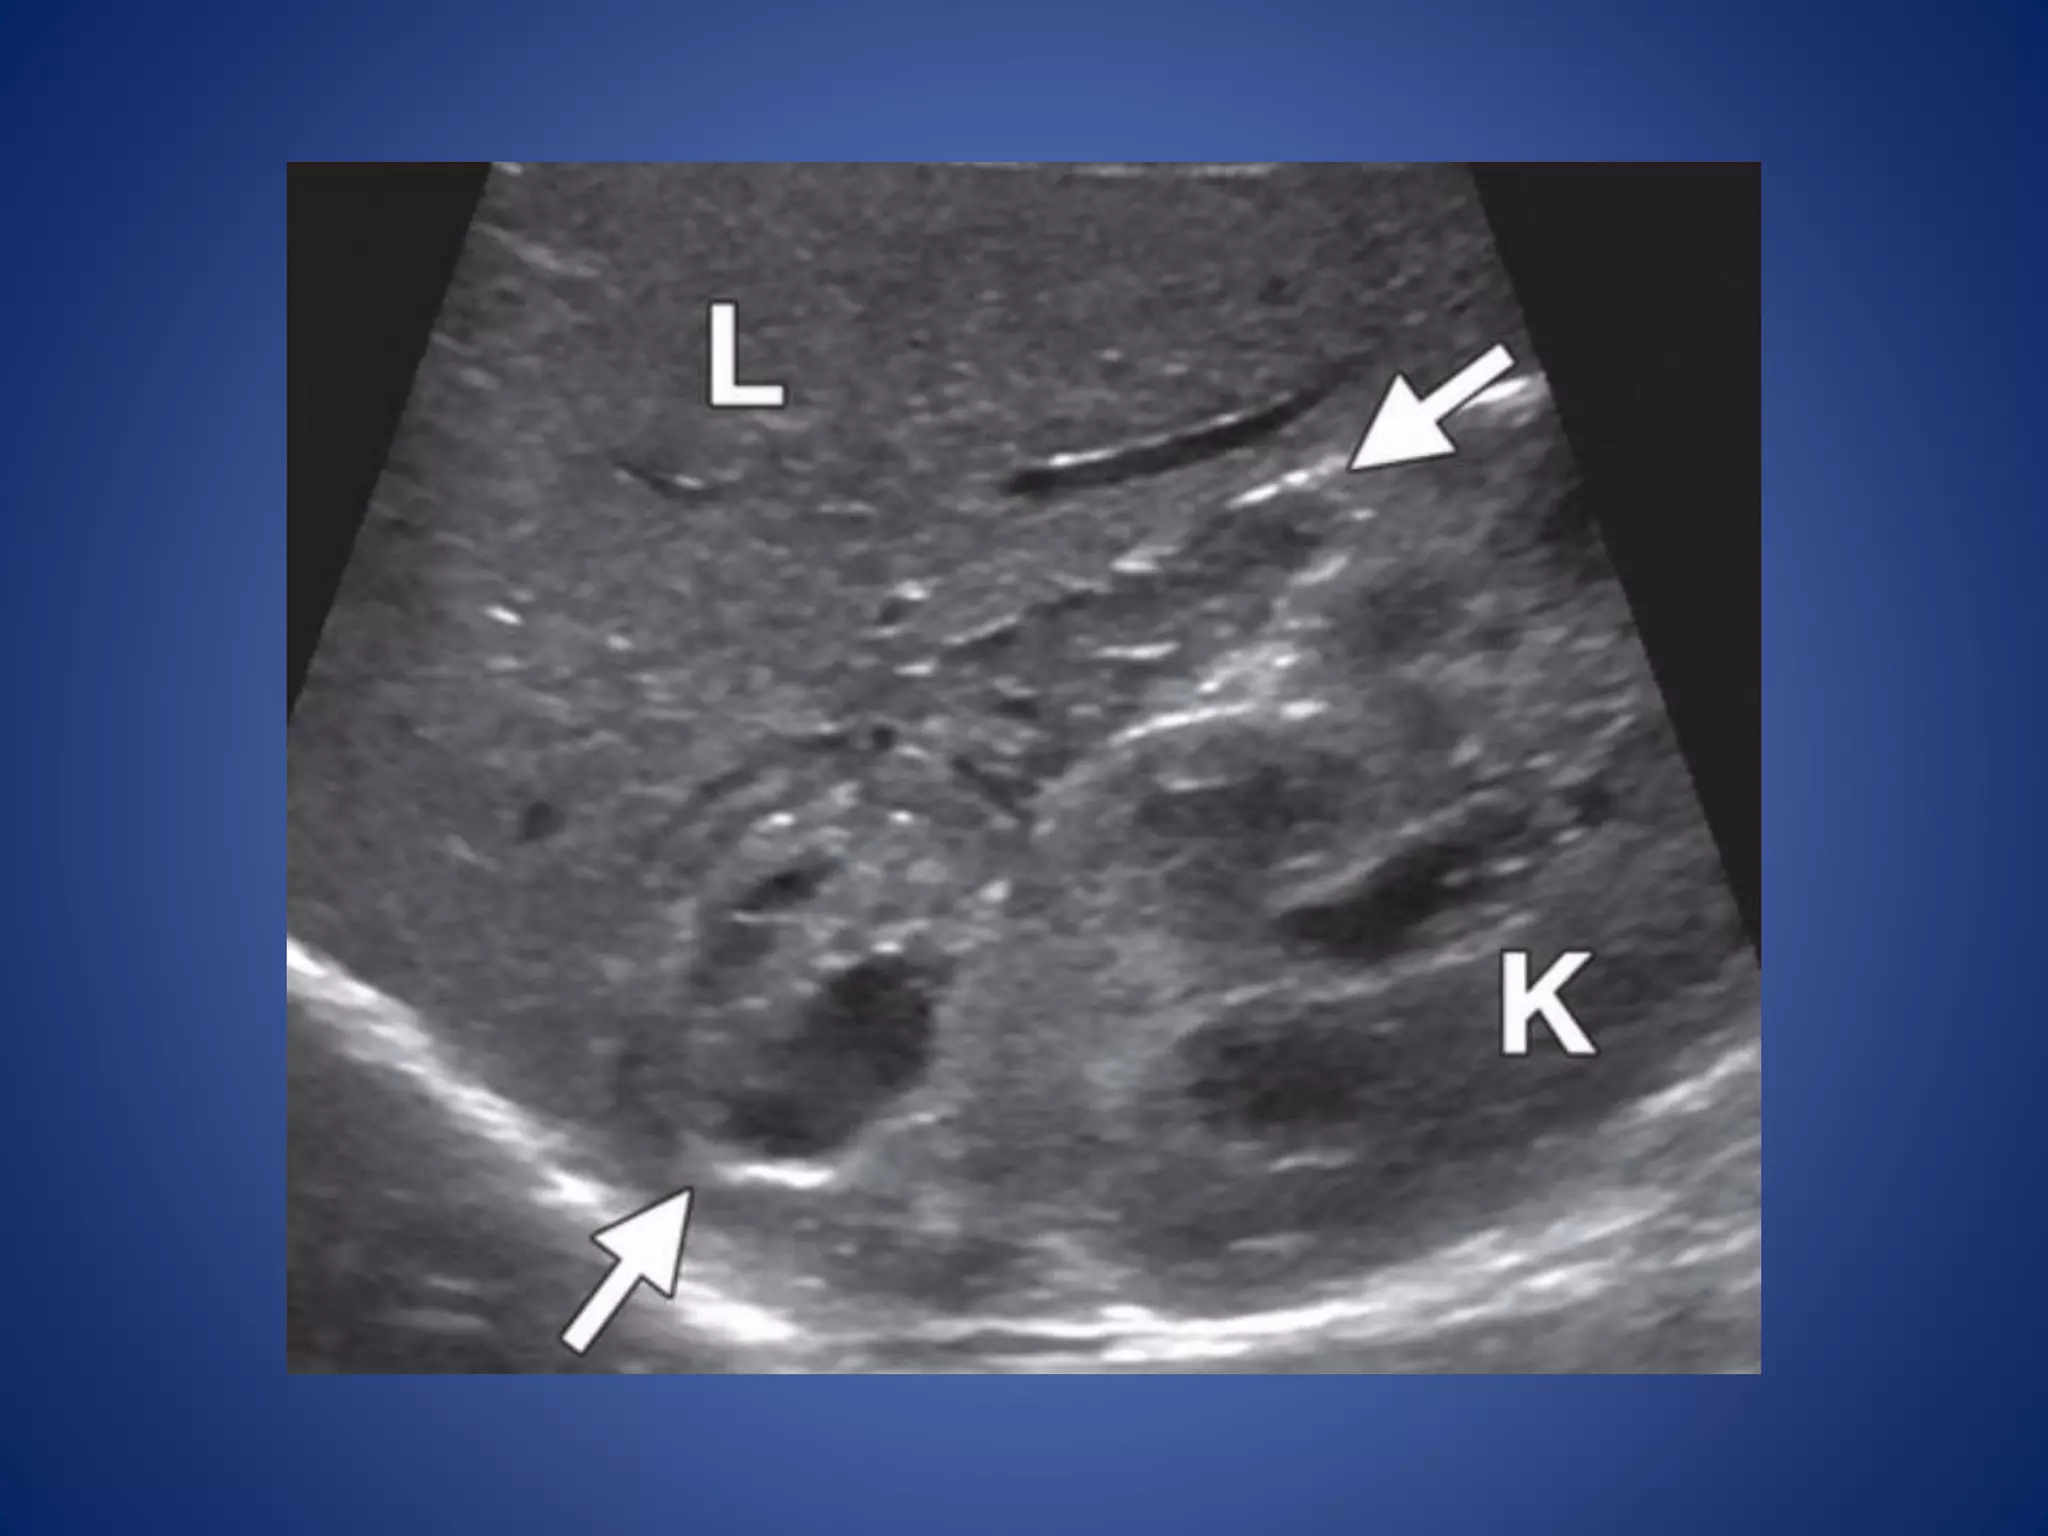

• 54.

Testicular adrenal resttumors in adrenogenital syndrome are very common in boys with CAH. These tumors are small, generally multiple, and often bilateral. The involved testis may be enlarged, but its contour is not distorted. The masses are eccentric and commonly surround the mediastinum testis.

• 55.

Their appearance atUS is variable and depends on size. Smaller lesions (<2 cm) appear hypoechoic compared with the adjacent testicle, whereas larger lesions appear hyperechoic with posterior acoustic shadowing. At color Doppler imaging, vessels may be seen coursing through the lesion without being deviated by it.

• #42 ACN in a 23-month-old girl with virilization. (a) Longitudinal US image shows a large, lobulated adrenal mass (arrows) above the kidney